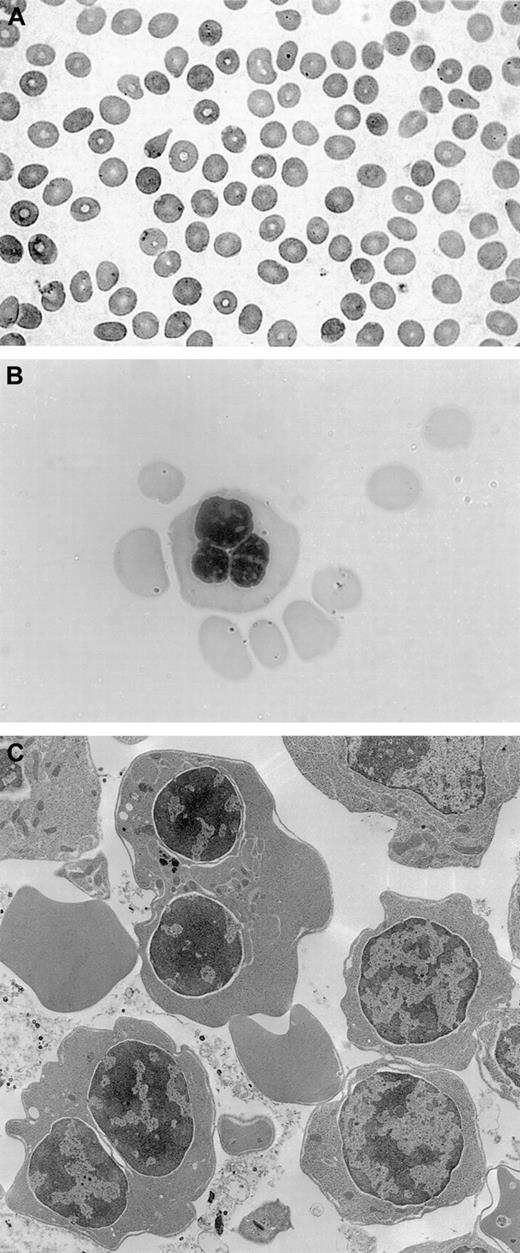

The patient underwent a bone marrow aspirate and biopsy, which showed normal myelopoiesis, dyserythropoiesis, and more than 20% binucleated erythroblasts. No karyotypic alterations were detected. Electron microscopy analysis revealed double membranes on the majority of erythroid precursors; the negativity of the Ham test oriented to a diagnosis of CDA type II with variant features.14Peripheral blood smear, bone marrow aspirate, and electron microscopy findings are shown in Figure 1.

(A) Peripheral blood smear, showing macrocytosis. (B) Bone marrow aspirate with a multinucleated erythroblast. (C) Electron microscopy findings with evidence of double membranes on erythroid precursors.